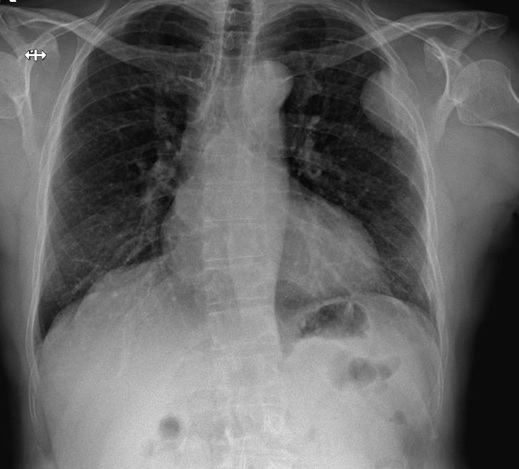

En la exploración física destaca un dolor al realizar la bidepstación y dolor a la palpación de apófisis espinosas dorsales D6 hasta L1 e imposibilidad a la movilización a la flexión, extensión y rotación de columna, resto sin alteraciones.

Se realiza radiografía de lumbar, dorsal y destaca chafamiento de D4 y una disminución radiodensidad ósea en todos los cuerpos vertebrales.

A su llegada a urgencias se realiza analítica complementa y una tomografía computerizada dorsolumbar objetivandose metástasis óseas cervical, dorsal D4, D6, D12 y afectación cuarto arco costal, se decide ingreso para estudio diagnosticándose un mieloma múltiple.